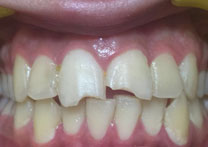

(3)Dental Veneers

Before Treatment

After Treatment

Patient with a complaint of rotated upper left lateral incisors. Veneers placed for the treatment of the rotated upper left lateral incisors.